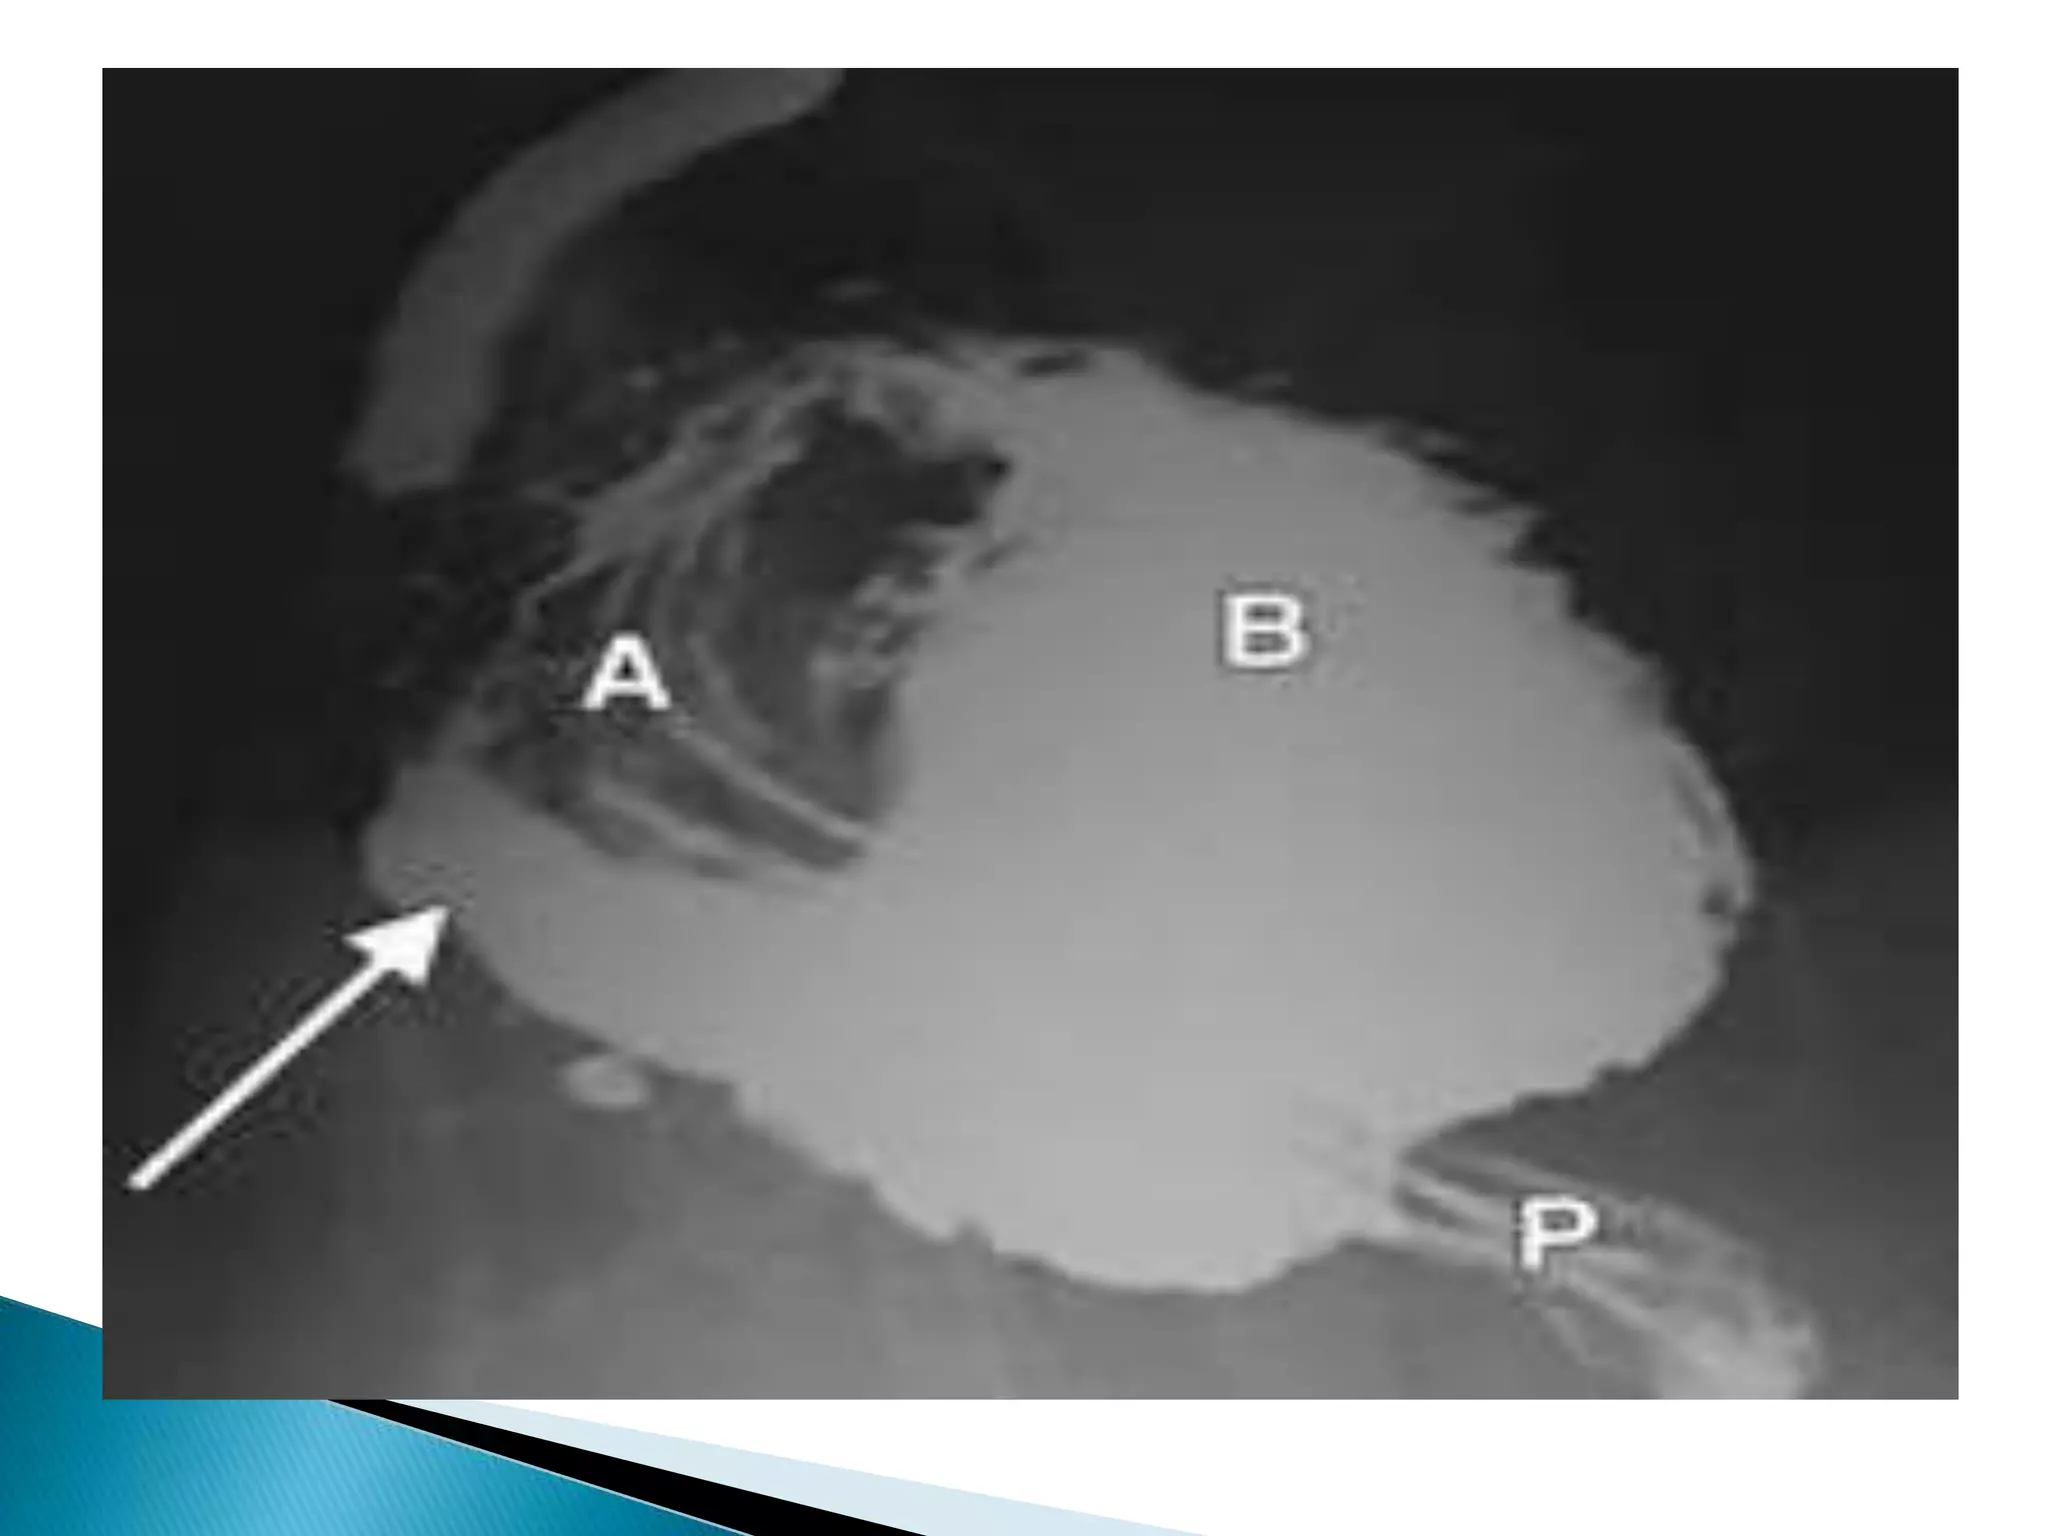

Ba contrast enema

contrast-filled rectum

illustrates the "bird's beak"

sign (white arrow),

corresponding to the

luminal narrowing at the

site of sigmoid obstruction.

This is the characteristic

presentation of a sigmoid

volvulus